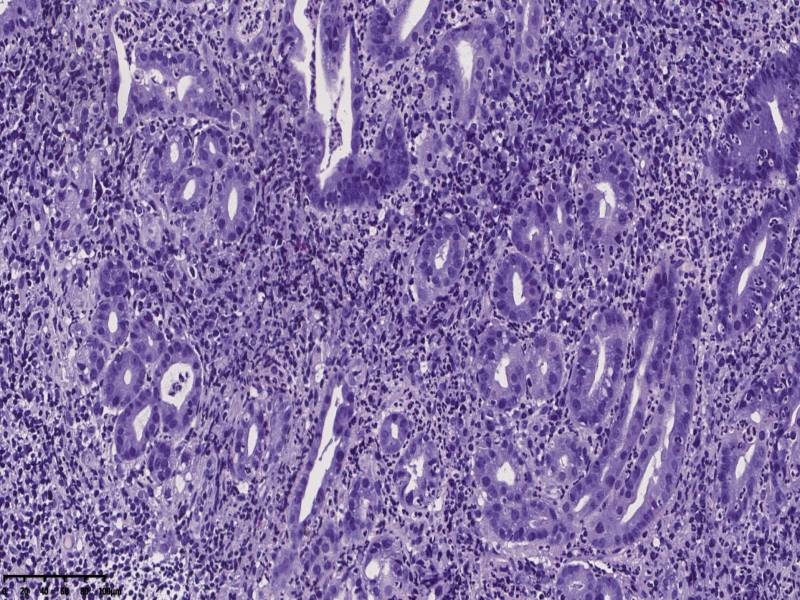

镜下,胃体型粘膜组织,炎症明显,有活动性炎,部分腺体形态不规则,呈角,上皮细胞单层,有异型,但是炎性反应性增生也不除外。

对比牵手癌还是有差距,不够诊断。254320

胃体:慢性胃炎,低级别上皮内瘤变,局灶腺体高级别上皮内瘤变伴畸形腺体(跳跃分

布),符合局灶黏膜内癌变(牵手癌);KI67:60%,CK7:部分+,CK20:表层腺体+,MUC5:

30%,MUC6:60%+,Villin5%,CDX-2 -,p53 60%,CEA 10%, SYN 散在+,10%;